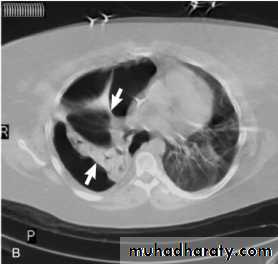

Pneumomediastinum.

Vertical dark (lucent) lines representing air within the mediastinum are usually seen at or above the level of the aortic arch.

On the posteroanterior view (A), these can be seen extending up into the lower cervical soft tissues (arrows).

On the lateral view (B), dark linear air collections can be seen in front of and behind the trachea.